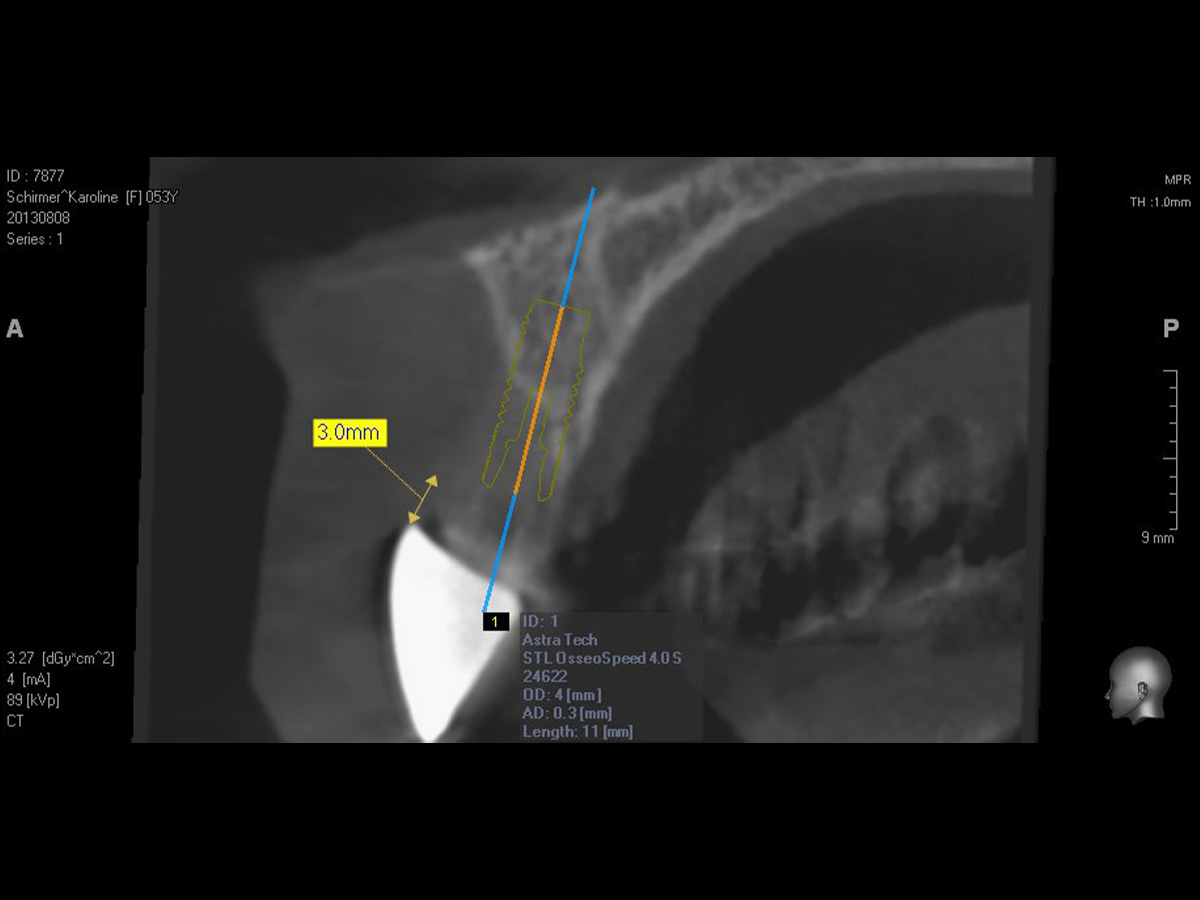

Abbildung 5

DVT, Knochendefizit in horizontaler und auch vertikaler Dimension.